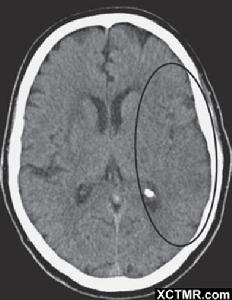

大腦中動脈閉塞早期CT平掃,出現患側腦島、最外囊和屏狀核密度減低,與鄰近腦白質密度相仿的現象。是島葉皮質缺血的特徵性表現,預示著大面積大腦中動脈梗死。

島帶徵MCA缺血發作時,CT平掃基底節層面見腦島側面灰質-白質界限不清。